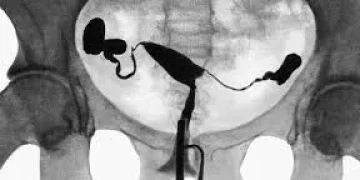

Гистеросальпинография, относящаяся к диагностике женской репродуктивной системы, является ещё одним методом лучевой диагностики.

При проведении рентгенографии яичников следует учитывать как анатомические особенности, так и потенциальные патологии. Например, рентген может использоваться для анализа состояния перитонеума или для исследования опухолевых изменений. Яичники размещаются глубоко в малом тазу, и их рентгенография может потребовать специальных приемов для получения четких изображений, таких как контрастные вещества или другие методы визуализации в комплексе с рентгеном.